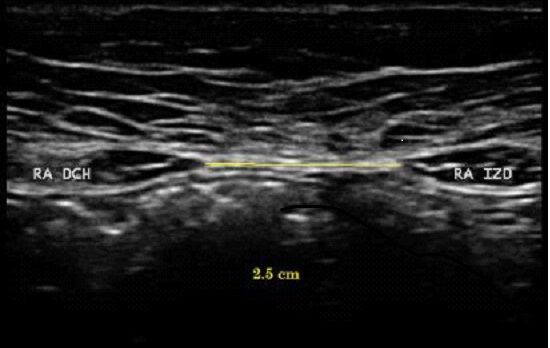

distancia entre rectos abdominales. ecografía.

Más de 2-2,5 cm de separación a nivel del ombligo (o por encima/por debajo). Puede haber separación en varios niveles: supraumbilical, umbilical y infraumbilical.